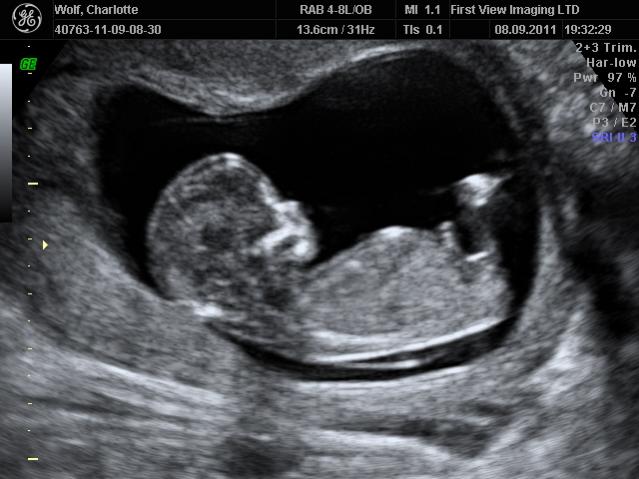

Skull Theory Gender Ultrasound

Skull Theory Gender Ultrasound Photos

Thumb Sucker... Skull Theory Gender Guesses? - YouTube

Skull Theory Gender Guesses? Genealogy09. Subscribe Subscribed Unsubscribe 0 0. Loading Loading Working Add to. 21W2D- 1st Ultrasound- Finding out the gender of our baby! - Duration: 7:16. ourlittlemushroom 156,545 views. 7:16 ... View Video

Skull Theory Gender Prediction! - YouTube

Skull Theory Explained: http://www.babble.com/pregnancy/skull Daily Vlogs: http://www.youtube.com/user/livinglexi MY STORE!!: https://jessamae.kitsylane.com My Other Channel: http://www.youtube.com/user/ihatekiax3 Instagram: http://instagram.com/xkiax3 Facebook: https://www ... View Video